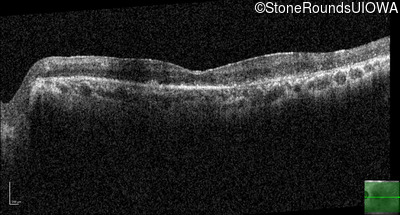

Age at visit: 62 years

OD OS

This 62 year old man had poor night vision as a teenager and developed difficulty with his peripheral vision in his early forties. His parents both grew up in the small village in Taiwan.

Diagnosis & molecular findings

Disease Gene Allele 1 variant(s) Allele 2 variant(s) Inheritance mode

AR Retinitis Pigmentosa EYS Cys2139Tyr TGT>TAT Cys2139Tyr TGT>TAT AR